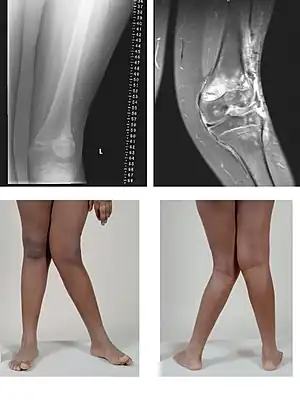

| A very severe case of genu valgum of the left knee following bone cancer treatment | |

Genu valgum, commonly called "knock-knee", is a condition in which the knees angle in and touch each other when the legs are straightened.[1] Individuals with severe valgus deformities are typically unable to touch their feet together while simultaneously straightening the legs. The term originates from the Latin genu, 'knee', and valgus which means "bent outwards", but is also used to describe the distal portion of the knee joint which bends outwards and thus the proximal portion seems to be bent inwards.

Mild genu valgum is diagnosed when a person standing upright with the feet touching also shows the knees touching. It can be seen in children from ages 2 to 5, and is often corrected naturally as children grow. The condition may continue or worsen with age, particularly when it is the result of a disease, such as rickets.[2] Idiopathic genu valgum is a form that is either congenital or has no known cause.